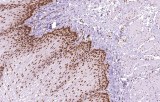

Primary antibodies for immunohistochemistry (IHC) with CE/IVD marking are essential reagents in diagnostic and research pathology, enabling the specific detection of target antigens in formalin-fixed paraffin-embedded (FFPE) tissue sections.

IHC using CE/IVD primary antibodies is a cornerstone in the characterization of gastrointestinal tumors. These antibodies assist pathologists in distinguishing epithelial from mesenchymal origins, determining tumor subtypes, and identifying primary sites in metastatic disease.

- In colorectal cancer, antibodies against cytokeratins (CK7, CK20) and transcription factors such as CDX2 facilitate accurate tumor classification and subtype differentiation.

- In gastric and esophageal adenocarcinomas, IHC highlights metaplastic and dysplastic changes, supporting early detection and prognostic evaluation.